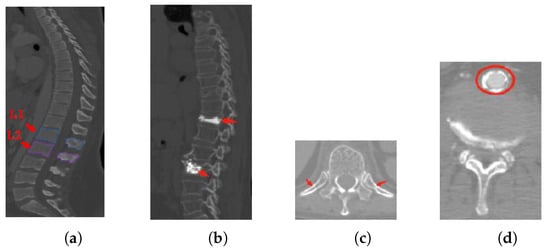

- Inter-class similarity: Shape and appearance similarities appear in the neighboring vertebrae from the sagittal view. It is difficult to distinguish the first lumbar vertebra (L1) and the second lumbar vertebra (L2) (as shown in Figure 1a);

- Unhealthy vertebrae, such as deformity or lesions (as shown in Figure 1b);

- Interference information: there are several soft tissues whose gray-scale is similar to the vertebrae area (as shown in Figure 1c,d).